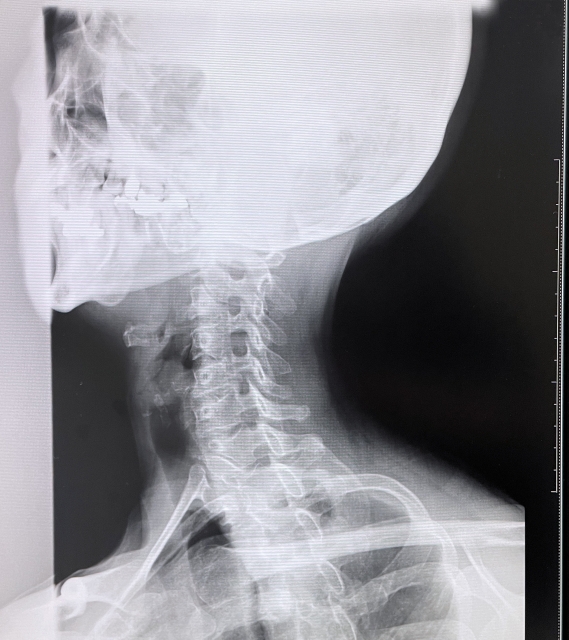

レントゲンは骨の変形・骨折を確認する検査 です。しかし交通事故のケガの多くは、

といった「軟部組織の損傷」 が原因です。これらはレントゲンでは写りません。

早期の適切な施術が、後遺症予防の鍵になります。レントゲンは骨の状態は確認できますが、筋肉・靭帯・神経・関節の細かい動きまでは検査ができません。